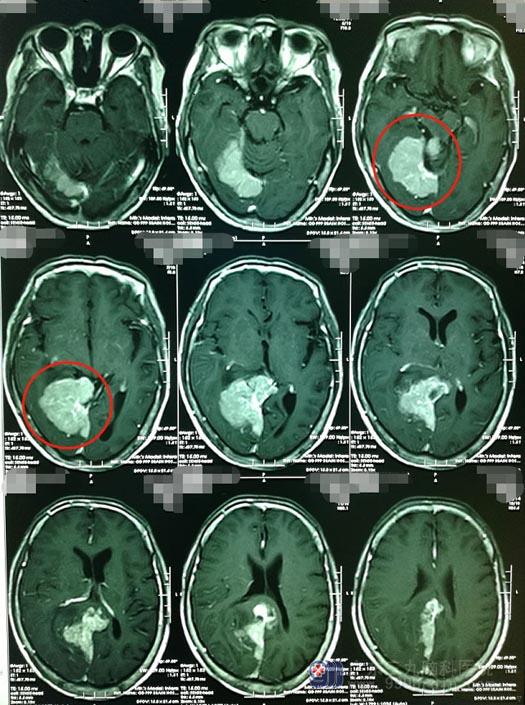

家属也一度陷入绝望,后来从了听朋友的建议,来到了广东三九脑科医院,并找到了医院副院长、神经外五科主任鲁明。鲁明仔细阅读了影像检查资料后,也同样认为是“右侧小脑幕上-右侧顶枕部及松果体区跨大脑镰-左侧顶部脑膜瘤”,肿瘤巨大,最大径超过7cm并且侵犯大静脉,右侧为主并生长到了对侧。

▲术前MRI